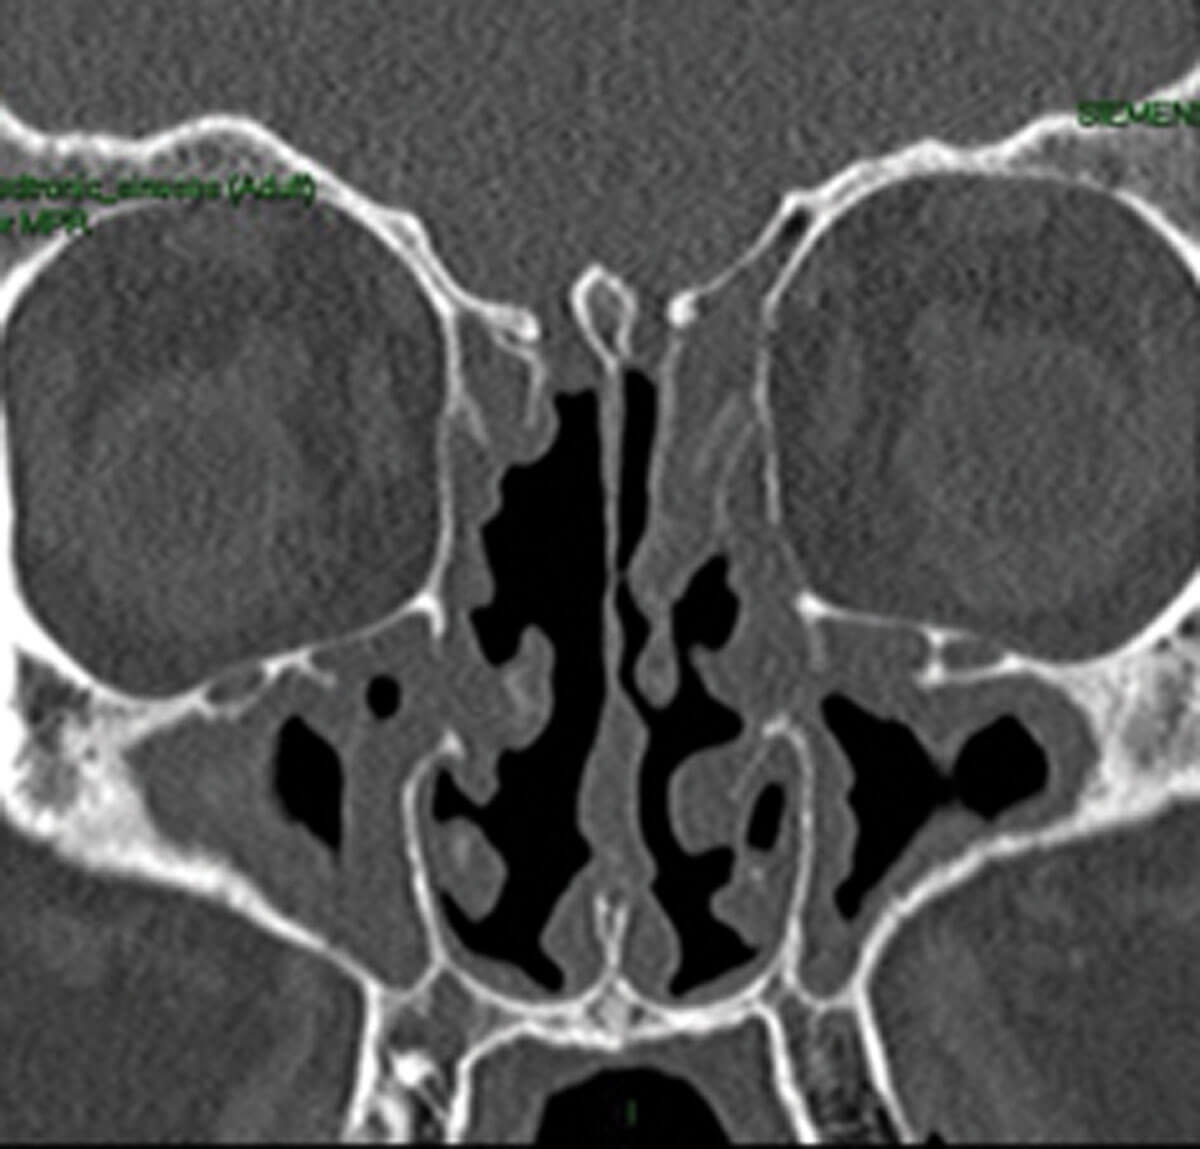

Supporting the notion that transmission to the OC due to mucosal oedema or polyps reduces quantitative olfaction is the positive response to oral and nasal steroids in many cases [1]. Furthermore, opacification of the olfactory cleft, as demonstrated on paranasal sinus CT imaging, has been shown to correlate well with olfactory function on psychophysical testing [2]. But it is not just oedematous mucosa that can occlude the olfactory clefts; thick eosinophilic mucin as seen in cases of non-steroidal exacerbated respiratory disease (NERD) and allergic fungal rhinosinusitis (AFRS) that can also accumulate in the olfactory clefts and spheno-ethmoidal recesses.

Radiological evidence of partial sinus surgery and middle turbinate removal.